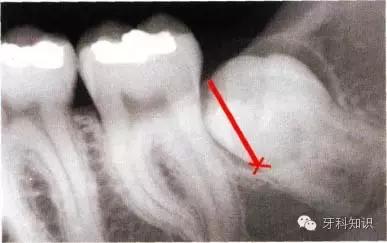

a下颌第三磨牙阻生。代表牙槽窝深度的红线表明从牙槽嵴顶到釉牙骨质界间在近中颊角方向上的距离。考虑到患者的年龄,阻生牙牙槽窝的近中骨壁较容易以第二磨牙牙根旁的硬骨板为基础分化再生。因此,该患者第二磨牙牙槽骨修复重建的预后较好

b阻生牙(牙合)面上覆盖的软组织较完整,牙槽窝与口腔不相通。切口起点应位于颞肌嵴黏膜,前庭沟的舌侧,朝向距离第二磨牙远中面15 mm外缘处向前切开